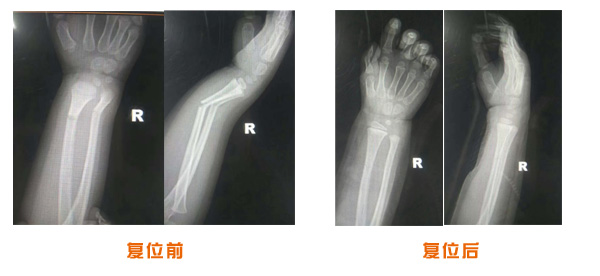

肘關(guān)節(jié)脫位骨折治療前后對比